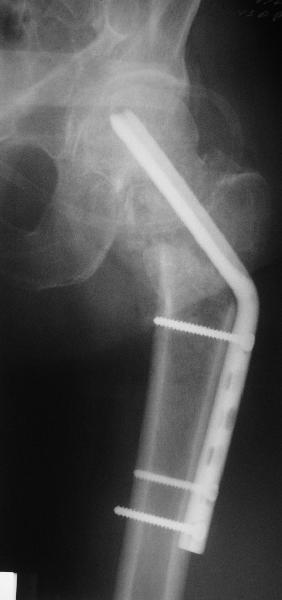

Re: Нелеченный перелом шейки бедра

Приветствую всех. Спасибо за активное участие в обсуждении. Выбрали вариант с остеотомией.

Снимки в приложении.

Надеемся на днях поднять на костыли.